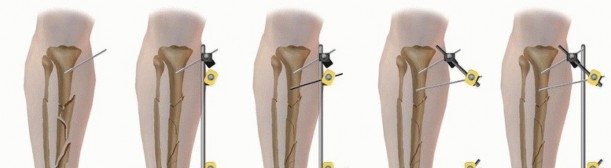

Monolateral Four-Pin Frame Application for Tibial Shaft Fracture Contemporary simple monolateral fixators have clamps that allow independent adjustments at each pin-bar interface, allowing wide variability in pin placement, which helps to avoid areas of soft tissue compromise. Because of this feature, simple four-pin placement may be random on either side of the fracture. ### Option 1 The initial two pins are first inserted as far away from the fracture line as possible in the proximal fracture segment and as distal as possible in the distal fracture segment ( TECH FIG 2A). A solitary connecting rod is attached close to the bone to increase the rigidity of the system. Longitudinal traction is applied and a gross reduction is achieved ( TECH FIG 2B-F). The intermediate pins can then be inserted using the pin fixation clamps attached to the rod to act as templates with drill sleeves as guides. These pins should not encroach on the open wound or severely contused skin in the immediate zone of injury. After placement of these two additional pins, the reduction can be achieved with minimal difficulty by additional manipulation of the fracture. Once satisfactory reduction has been accomplished, the clamps are tightened and reduction is confirmed via fluoroscopy. ### Option 2 Alternatively, all the fixation pins can be inserted independent of each other, with two pins proximally and two pins distally ( TECH FIG 3). The two proximal pins are connected to a solitary bar and the distal two pins are connected to a solitary bar. Both proximal and distal bars are then used as reduction tools to manipulate the fracture into alignment. Once reduction has been achieved, an additional bar-to-bar construct between the two fixed-pin couples is connected. Reduction is confirmed under fluoroscopy. 538

### TECH FIG 2 • Placement of a simple four-pin monolateral fixator. A. Two pins are placed on either side of the fracture as far from the fracture as possible. A connecting bar is then attached to the two pins (B) and a gradual reduction is performed (C-F). Two pins are then placed as close to the fracture as possible on either side, after longitudinal traction has accomplished a reduction. The inner pins are then attached, and the reduction is fine-tuned. 539

### TECH FIG 3 • Alternative method for simple four-pin monolateral fixator. A,B. Once the bar is attached, two intercalary clamps can be positioned as templates for the placement of the interior pins. C. Final construct after interior pin placement. D. The proximal and distal two pins can be attached to each other by a solitary bar. These bars can then be used as tools to reduce the fracture. E. The two bars are then connected by a solitary bar, and the fracture reduction is maintained. F,G. Closed fracture with associated compartment syndrome is reduced and stabilized using a four-pin fixator with a double stack bar for stability, and the foot is spanned to maintain a plantigrade foot. H. Similar tibial fracture reduced with four pins and a single bar. Note pins out of plane to each other to facilitate ease of pin insertion.